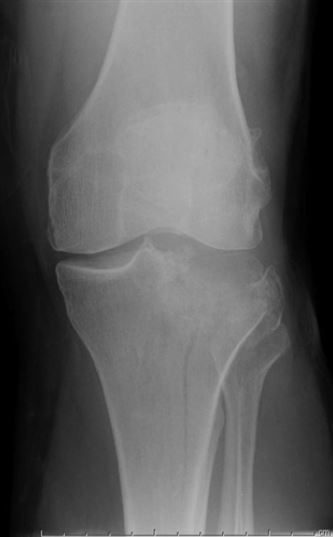

A 45-year-old patient sustains the injury shown in figure A. What radiographic finding most highly suggests a lateral meniscal injury?

This is a Shatzker II tibial plateau fracture.

Gardner (2005) showed that:

1. Joint depression of > 6 mm

2. Joint widening of > 5 mm

was associated with lateral meniscus injury 80% of the time